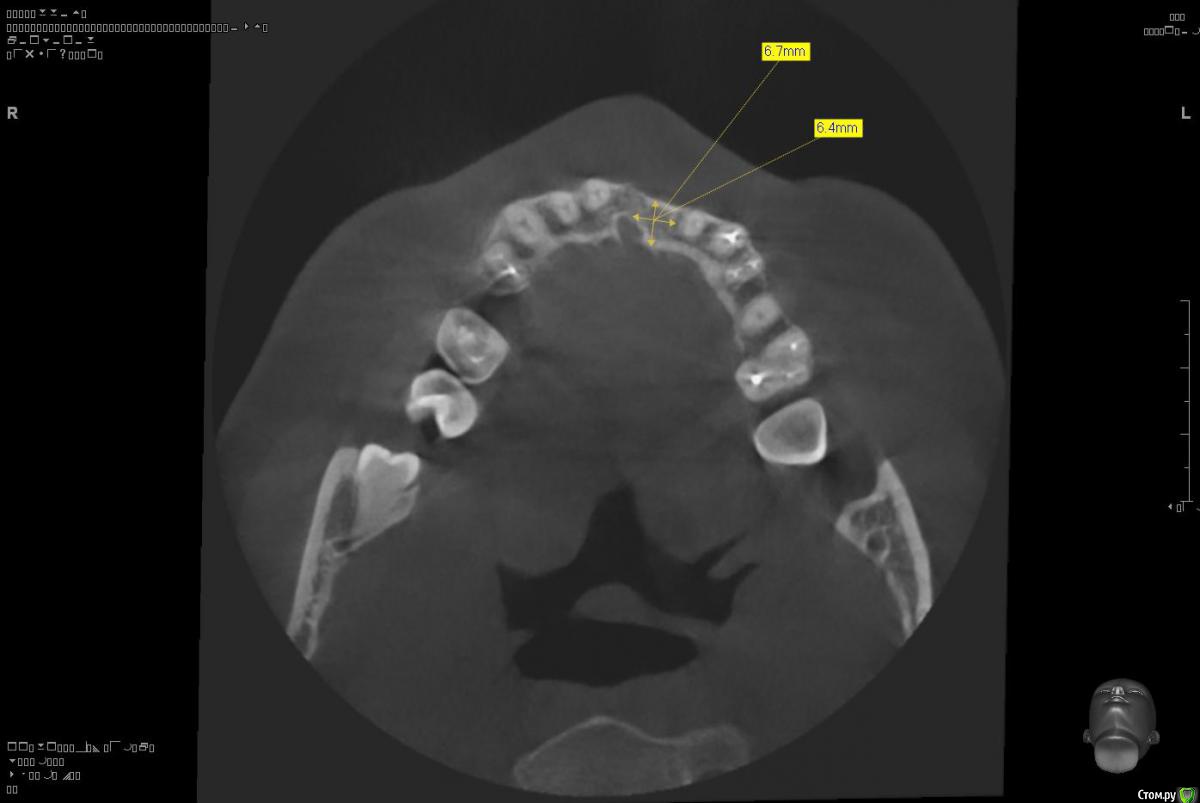

Platon Опубликовано 10 января, 2016 Поделиться Опубликовано 10 января, 2016 Здравствуйте.Помогите с планированием начинающему.Пациентка 38 лет. отсутствует 21. визуально в области 21 провал (фото нет, пока только кт). ходит с акриловой "птичкой"ортопед говорит: ставь, она к эстетике не будет предъявлять претензий))). с чем мне не хочется соглашаться(система ALPHA BIOкак правильно поступить?какие варианты рассматриваю:1. имплантация 3,75 на 11.5 SPI. ,+ временная коронка. Без какой либо пластики.2. костная пластика (мембрана,ксено,) без имплантации, сст, капа на 4 -6мес. потом имплантация + временная коронка3. имплантация, сст , временная коронка С учетом обстановки, прессинга, отсутствия опыта в аугментации, склоняюсь к третьему варианту. заранее спасибо за советы!удачного дня! Ссылка на комментарий

Platon Опубликовано 31 января, 2016 Автор Поделиться Опубликовано 31 января, 2016 Продолжение.не судите строго за фото, первый раз вообще фоткаю операцию)спасибо за советы.По порядку. После того, что мне написали, я решил все -таки уговорить на конусный имплантат (3.7-11.5 ImplantDirect). Также ортопед не хотел делать временную коронку, сказал что сделает каппу, птичку в топку -тоже сделали. Слизистая в области 21 была в рубцах. Исходя из этого всего я решил, коль временной коронки не будет, то сст подсаживать тоже не стану пока,(ортопеда уговаривал сделать временную коронку)))- торк был хороший 35-50н) для того чтобы сст попрактиковаться, но(((.в итоге, анестезия, разрез, сверло пилотное и сверло 2.2, далее расщепление с помощью набора майзенгер с использованием спредеров до нужного диаметра, установил имплантат, торк контролируемый, можно было подобрать любой) в итоге оставил 35. заглушка, совсем немного ксено, мембрана, ушился. ждем. Будет что-то типо каппы которая слегка отдавливает десну,формируя сосочки. не знаю, ни разу такую еще не видел.планирую на этапе раскрытия все-таки сст и временную коронку увидеть.вот. через 4 мес. выложу, что получилось) Если есть советы, критика, всему буду рад, спасибо 3 Ссылка на комментарий